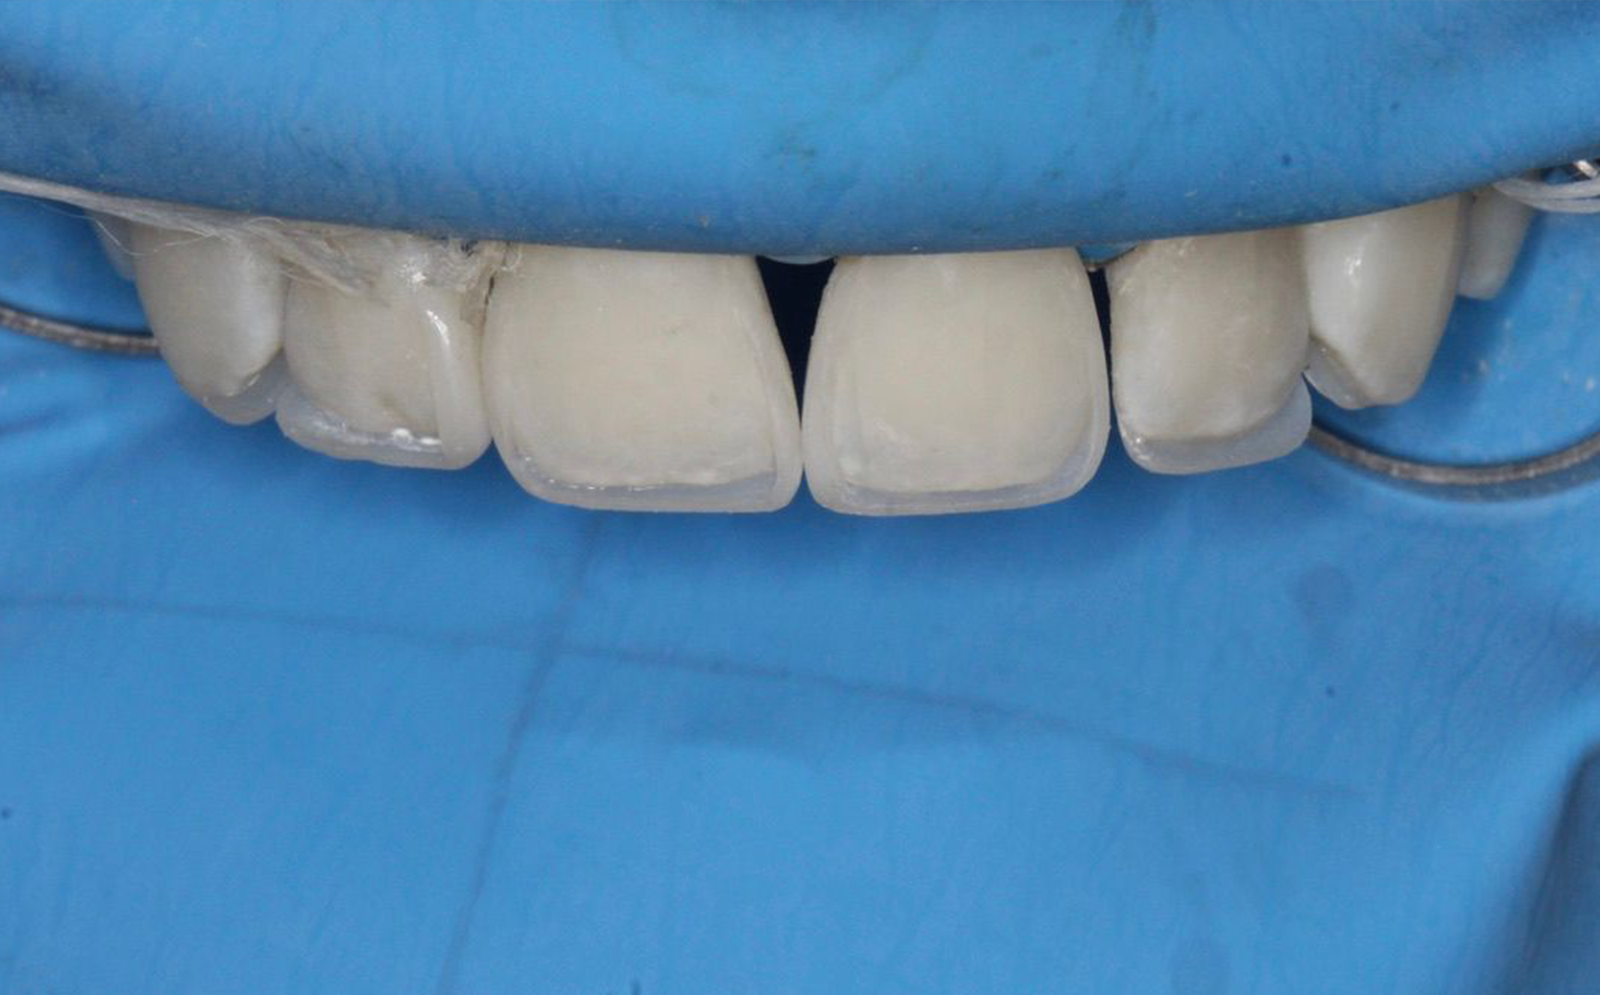

Antes

Procedimiento

Después